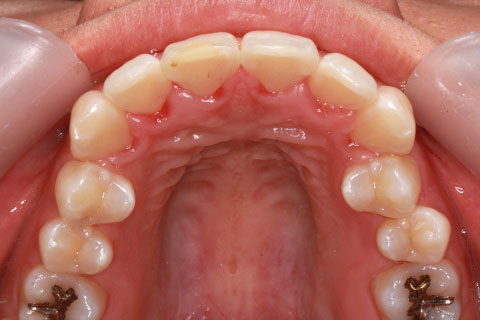

矯正期間24ヶ月

ハーフリンガル矯正3(上の歯のみ舌側矯正で治療)

治療前

治療中(開始直後)

治療中(開始半年後)

治療後

- 年齢・性別

- 25歳女性

- 治療期間

- 2年0ヶ月

- 抜歯

- 上下4番抜歯

- 治療費

- 110万円

- 備考

- 治療内容

- 施術の副作用(リスク)

- 表側矯正と比較して、力学的な操作性が複雑なため、ボーイングエフェクトを起こしやすい。